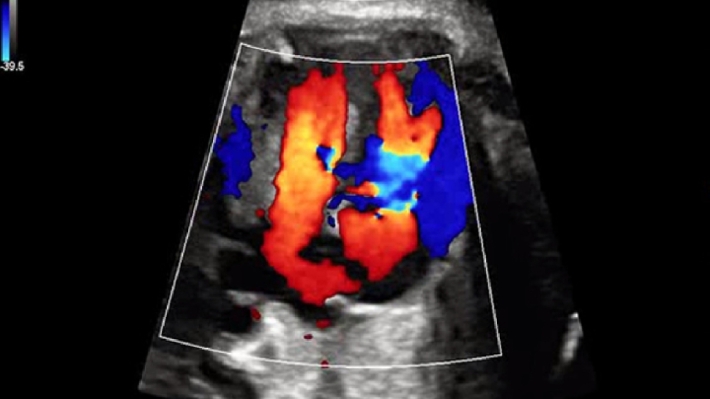

УЗИ-аппарат Mindray DC-70 — это современная ультразвуковая система экспертного класса, предназначенная для проведения диагностических исследований в различных областях медицины, включая кардиологию, акушерство и гинекологию, абдоминальные и сосудистые исследования. Аппарат сочетает высокое качество изображения с широким набором функциональных возможностей, что делает его эффективным инструментом для диагностики.

• Многофункциональность: Поддержка различных режимов сканирования, включая 2D, 3D/4D, цветное допплеровское картирование и другие, позволяет использовать аппарат для широкого спектра медицинских задач;

• HDR Flow — режим отображения кровотока с высоким временным и пространственным разрешением, обеспечивающий точную и однородную визуализацию сосудов, включая самые мелкие;

Изображения